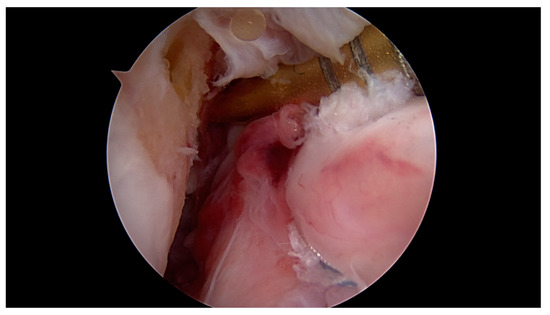

Primary Proximal ACL Repair: A Biomechanical Evaluation of Different Arthroscopic Suture Configurations

by Steffen B. Rosslenbroich, Andrea Achtnich, Cathrin Brodkorb, Clemens Kösters, Carolin Kreis, Sebastian Metzlaff, Benedikt Schliemann and Wolf Petersen

J. Clin. Med. 2023, 12(6), 2340; https://doi.org/10.3390/jcm12062340 - 17 Mar 2023

Purpose: Several suture techniques have been described in the past for direct ACL repair with poor healing capacity and a high re-rupture rate. Therefore, we investigated a refixation technique for acute primary proximal ACL repair. The purpose of this study is to [...] Read more.

Purpose: Several suture techniques have been described in the past for direct ACL repair with poor healing capacity and a high re-rupture rate. Therefore, we investigated a refixation technique for acute primary proximal ACL repair. The purpose of this study is to compare the biomechanical properties of different suture configurations using a knotless anchor. Methods: In this study, 35 fresh-frozen porcine knees underwent proximal ACL refixation. First, in 10 porcine femora, the biomechanical properties of the knotless anchor, without the ligament attached, were tested. Then, three different suture configurations were evaluated to reattach the remaining ACL. Using a material testing machine, the structural properties were evaluated for cyclic loading followed by loading to failure. Results: The ultimate failure load of the knotless anchor was 198, 76 N ± 23, 4 N significantly higher than all of the tested ACL suture configurations. Comparing the different configurations, the modified Kessler–Bunnell suture showed significant superior ultimate failure load, with 81, 2 N ± 15, 6 N compared to the twofold and single sutures (50, 5 N ± 14 N and 37, 5 ± 3, 8 N). In cyclic loading, there was no significant difference noted for the different configurations in terms of stiffness and elongation. Conclusions: The results of this in vitro study show that when performing ACL suture using a knotless anchor, a modified Kessler–Bunnell suture provides superior biomechanical properties than a single and a twofold suture. Within this construct, no failure at the bone–anchor interface was seen. Clinical relevance: Since primary suture repair techniques of ACL tears have been abandoned because of inconsistent results, ACL reconstruction remains the gold standard of treating ACL tears. However, with the latest improvements in surgical techniques, instrumentation, hardware and imaging, primary ACL suture repair might be a treatment option for a select group of patients. By establishing an arthroscopic technique in which proximal ACL avulsion can be reattached, the original ACL can be preserved by using a knotless anchor and a threefold suture configuration. Nevertheless, this technique provides an inferior ultimate failure load compared to graft techniques, so a careful rehabilitation program must be followed if using this technique in vivo. Full article

Show Figures

Figure 1